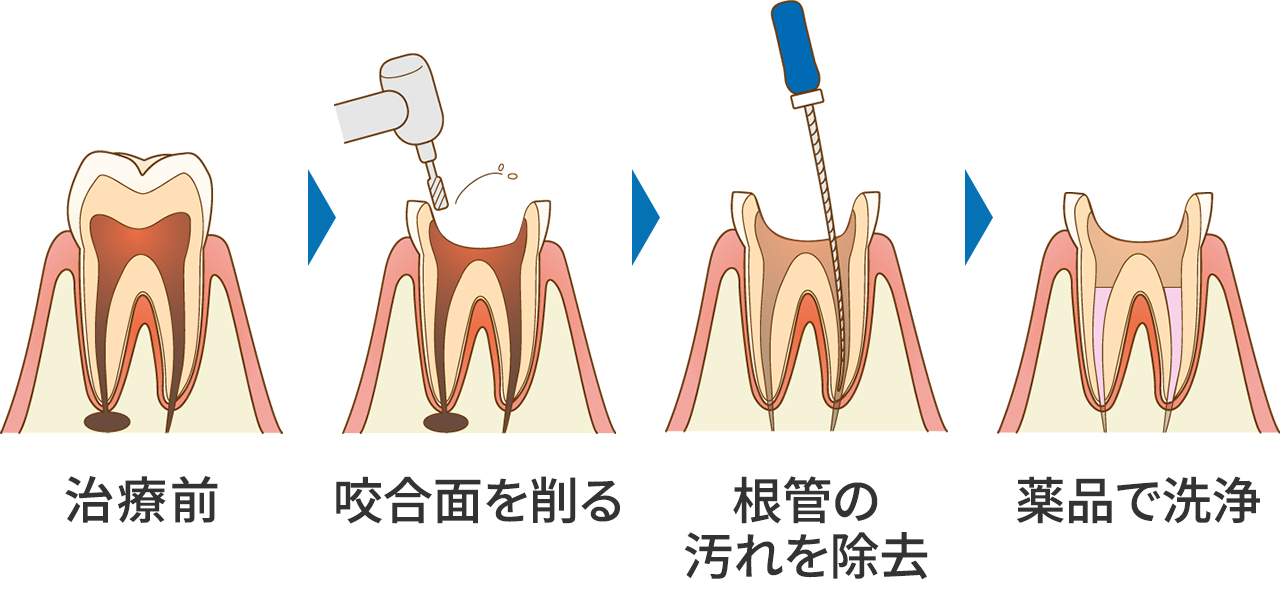

根管治療

ROOT CANAL

根管治療について

進行したむし歯には根管治療を行います

むし歯が進行し神経にまで達した場合、根管治療を行う必要があります。根管とは、歯の内部にある神経や血管が通った部位のことです。根管は細く複雑な構造であるため、精密な治療が求められます。当院では、豊富な経験のある歯科医師が診療にあたり、辛い症状を和らげながら丁寧に治療いたします。

根管治療1回目~根管内のお掃除・殺菌~

根管治療の初回では、根の中の神経や感染部分を丁寧に清掃し、細菌を取り除きます。

清掃後は専用の薬液で根管内を洗浄・殺菌し、その日の処置は仮歯を装着して終了です。

保険診療の場合はこの治療を複数回に分けて行います。回の来院は、治療後の症状を確認するため、約1週間後を目安に調整します。